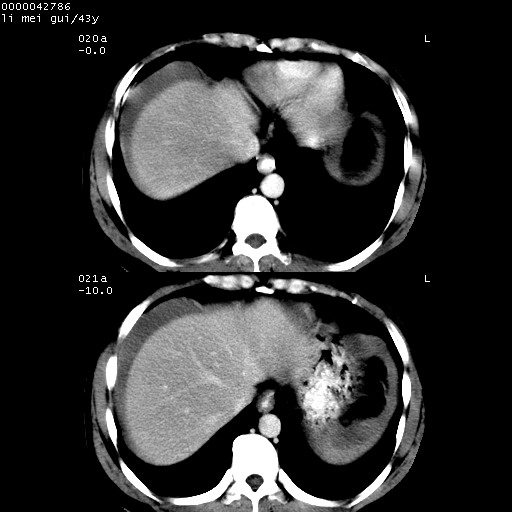

| 患者,男,43岁。突发腹痛2小时,面色苍白,难以平卧。自述近期无明确外伤史,为摩托车驾驶员。 腹部b超检查:脾脏中上极回声异常,肿瘤待排。 临床诊断:腹痛原因待查。 上中腹部ct轴位平扫+增强扫描(层厚10mm,螺距1.0,重建间隔10mm),图像如下: ![]() ![]() ![]() ![]() ![]() ![]() ![]() ![]() ![]() ![]() ![]() ![]() ![]() ![]() ![]() ![]() ![]() ![]() ![]() ![]() ![]() ![]() ![]() ![]() ![]() ![]() ![]() ![]() ![]() ![]() ![]() ![]() ![]() ![]() ![]() zrs发言:支持脾破裂 wwp发言:支持脾破裂并腹水。 xulianj发言:脾脏肿瘤破裂可能性大 zsl6918发言:不像肿瘤出血,考虑还是与外伤后引起的慢性出血有关 zzyy发言:平扫见肝周及脾周积液,脾内密度不均。脾内肿瘤较少见。还是外伤性脾破裂。 沈丘东方医院发言:脾门区一个不均匀强化病灶与其周液体相连多考虑脾占位破裂出血 yixianman001011发言:脾破裂并腹水是可以肯定的,具体原因多以肿瘤性破裂出血,脾脏淋巴瘤可能性大. 结果: 术后,经详细询问患者,其仔细回忆:一月前骑摩托时左侧腰部与别人有“轻微”触碰,因责任在自已,当时又无明显不适,未引起注意。 临床术后诊断:脾破裂并失血性休克(1.外伤性迟发性脾破裂。2.脾脏肿瘤破裂?) 术后标本病检:脾破裂并出血,未见明显肿瘤成份。 原贴地址:http://www.radinet.com.cn/forum_view.asp?forum_id=4&view_id=34070 |